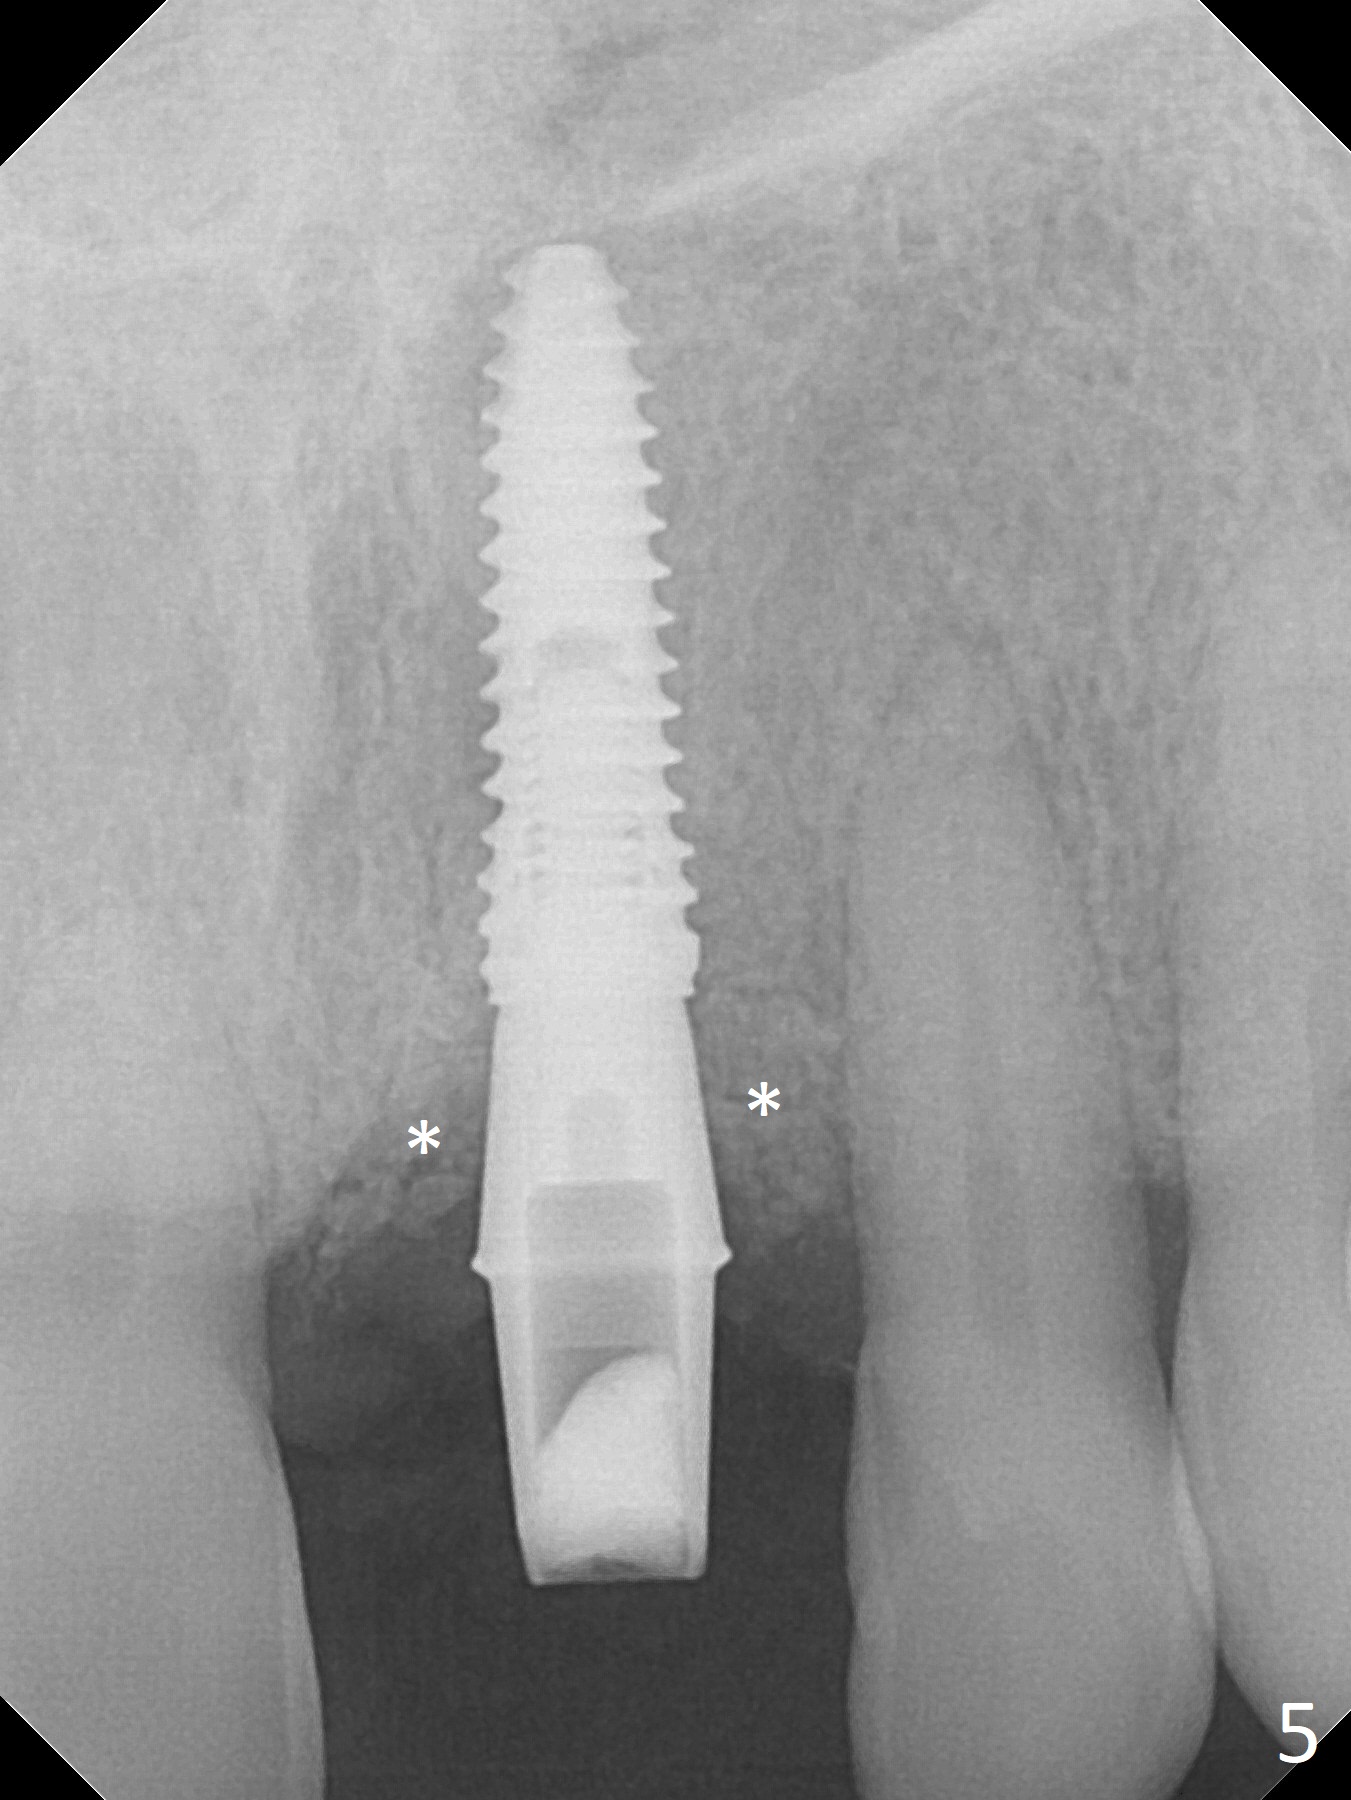

Preop examination shows mobility I of the teeth #8 and 10 and apparent occlusal trauma from #22-26 implant bridge. After occlusal equilibrium, incision reveals low, but moderate ridge at #9 (Fig.1). Fig.2a is a cross section of a normal upper incisor socket with thin buccal plate (B) and thick palatal one (P). It is difficult to initiate osteotomy in the oblique palatal wall when the buccal plate is resorbed (Fig.2b). In this case with horizontal buccal and palatal plate bone loss, the socket bottom is flat (Fig.2c), easy for osteotomy (Fig.2d green arrow, Fig.3). The initial osteotomy deviates mesial (Fig.3). To avoid perforation into the Incisive Canal, the trajectory is changed (Fig.4). After use of the final drill (3 mm), the coronal Incisive Canal is perforated. Following placement of a 3.5x13 mm implant and 4.5x5.5(4) mm abutment, Vanilla Graft is placed (Fig.5 *) to repair the perforation. Retrospectively, the coronal end of the Incisive Canal is revealed at incision (Fig.1 *). The initial osteotomy should be slightly more distal (Fig.3 black line). The buccal plate looks bulky due to placement of the abutment and bone graft 1 week postop (Fig.6,7 (crown dislodgement)). The bone graft appears to remain in place 2 months postop (Fig.8). Impression is taken because of instability of the immediate provisional (Fig.9 after Laser gingivectomy). The gingiva and buccal plate remain healthy 4.5 months postop (Fig.10). A permanent crown is cemented (Fig.11).